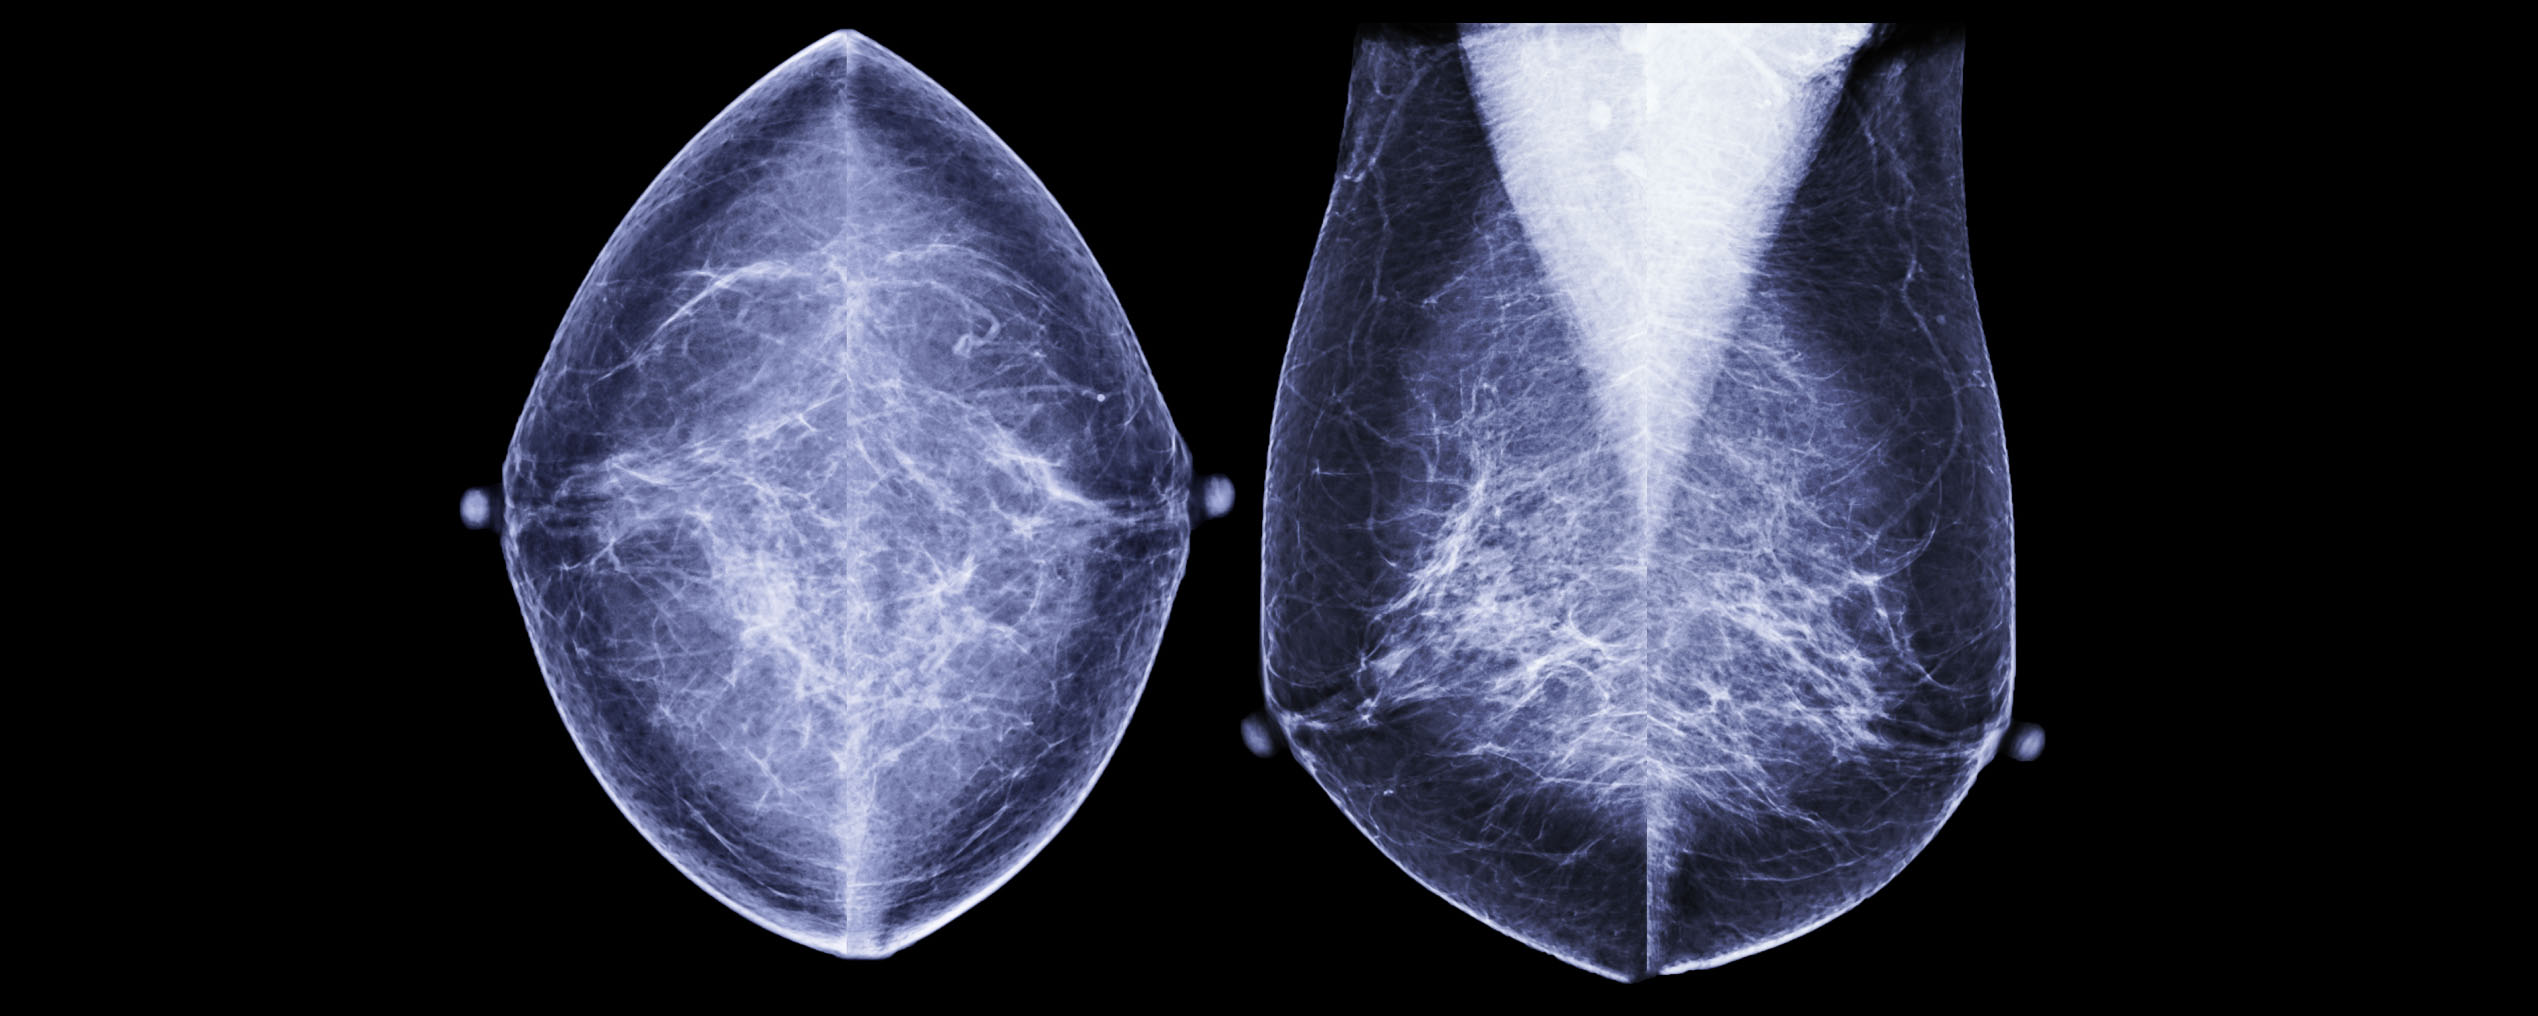

ARTICLEA transformative breast cancer treatment that works for patients across multiple ethnicities and countries

Meet Adjutorium, a powerful new algorithm that can help physicians identify the patients that will benefit most from adjuvant therapy.